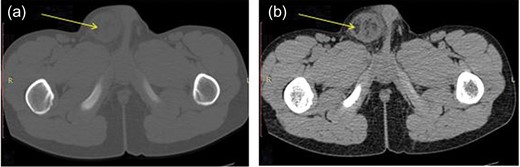

A 13-year-old boy was presented to the pediatric emergency with a 2-week history of swelling of the right scrotal contents, of simple evolution. During the previous 48 h, his symptoms worsened by the appearance of acute scrotal pain motivating him to consult. He had no known testicular or scrotal abnormalities. There were no fevers, abdominal pain, nausea or vomiting. He had no significant past medical, past surgical or family history. The examination revealed a soft abdomen but with an erythematous right hemiscrotum that was swollen, tense and particularly painful during its palpation (Fig. 1). A transillumination test was positive. The left testis was confirmed to be in the left scrotum and it was normal. Laboratory studies found a hemoglobin and a hematocrit level of 12.5 g/dl and 34.4%, respectively, and a white blood cell count of 11 210/μl with 80% neutrophils. C-reactive protein level was 11 mg/l. Electrolytes were within normal limits and urinalysis exam was negative. Ultrasonography was concluded as a strangulated inguinal hernia with a fluid collection around the right testis, but testicular torsion and torsion of appendages were not ruled out. We performed a scrotal CT scan that found an image of a greasy substance in the scrotum protruding from the abdomen through the right inguinal canal (Fig. 2). We suspected an omentum incarcerated in inguinal hernia mimicking an acute scrotum. A decision to explore the right hemiscrotum was made. Surgery was proceeded using a transinguinal approach. The right inguinal canal was opened through an inguinal skin crease incision. On opening of the hernial sac, 10 ml of fluid was cleared out. On further exploration, a segmental infarct of the omentum was found, but most of the part was normal (Fig. 3). The testis was showed to be normal. Surgical resection of the affected omentum and reduction of the rest of the omentum back into the peritoneal cavity was performed. High ligation herniotomy was done. The patient had complete resolution of symptoms 1-month postoperatively.

CT scan before (a) and after (b) intravenous contrast, showed an image of a greasy substance in the scrotum.